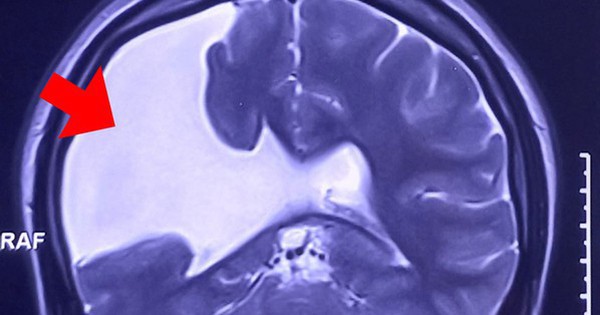

Tại Bệnh viện Đa khoa Tâm Anh, kết quả chụp MRI 3 Tesla (loại máy thế hệ mới nhất) cho thấy não chị N. có một khe nứt lớn kéo dài từ vỏ não đến não thất nằm bên bán cầu não phải.

Chị N. bị nứt não bẩm sinh từ nhỏ nhưng không biết, đến nay vết nứt mở rộng, gây động kinh, co giật nghiêm trọng. Nhiều năm qua, chị điều trị co giật, động kinh với liều thuốc cao nhất nhưng không có kết quả.

“Đa số trường hợp dị tật nứt não nhỏ không làm gia tăng áp lực nội sọ đến mức phải can thiệp. Trường hợp của chị N. là đặc biệt, vết nứt não mở rộng, dịch não tủy tràn vào làm gia tăng áp lực nội sọ, chèn ép lên bề mặt vỏ não gây động kinh. Giải pháp tối ưu là phẫu thuật giải áp, sau đó tiếp tục theo dõi, điều trị bệnh động kinh” – bác sĩ Sĩ nhấn mạnh.